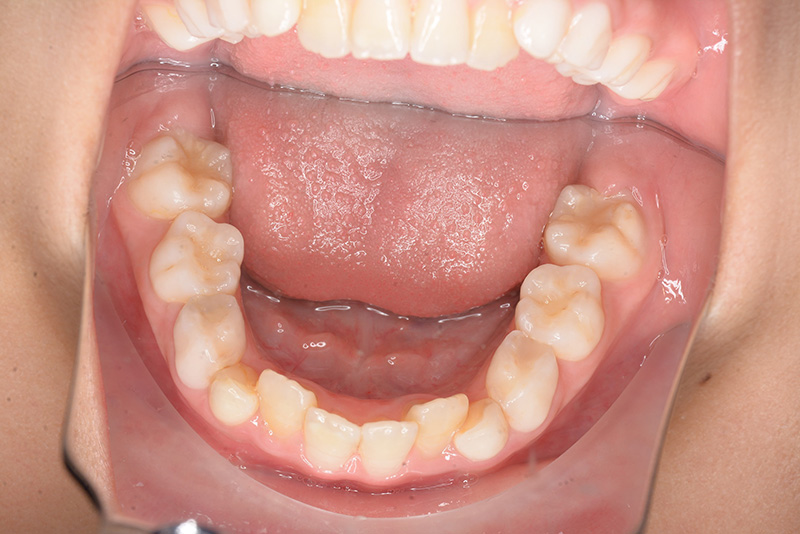

| 口腔内所見 | over jet 2.5mm、over bite 2.0mm、右側大臼歯関係はEnd on class Ⅱ、上顎左側Eは早期喪失により左側大臼歯関係はFull classⅡ、右側Eは6の異所萌出により歯根吸収が進行したため一般歯科医院にて抜去済みであった。 |

| パノラマ所見 | 上顎両側6、特に左側6は近心傾斜が認められ、両側5の萌出スペース不足が認められた。 |